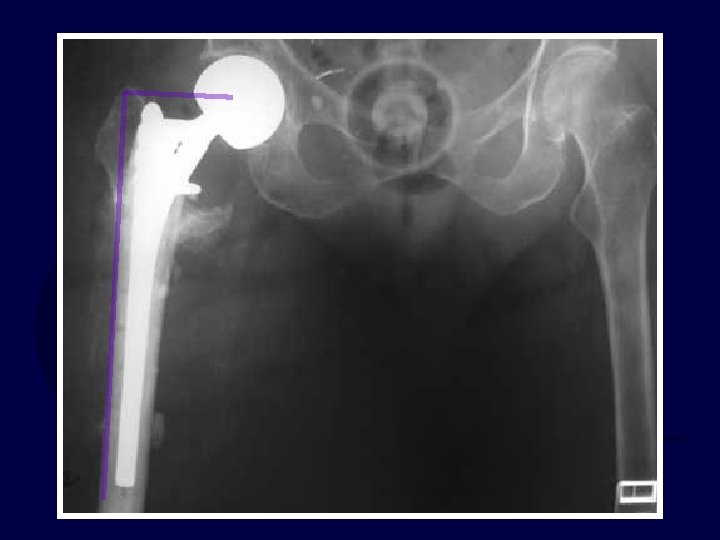

71 yo renal txplnt pt c CHF What to do? ?

If my patient, I would use: 1. Hip screw and sideplate 2. Hip screw and IM nail (TFN) 3. Reconstruction Nail (2 proximal medullary-cephalic screws) 4. Blade Plate 5. Other

percutaneous reduction

Uneventful Healing, WBAT 6 wks 12 wks